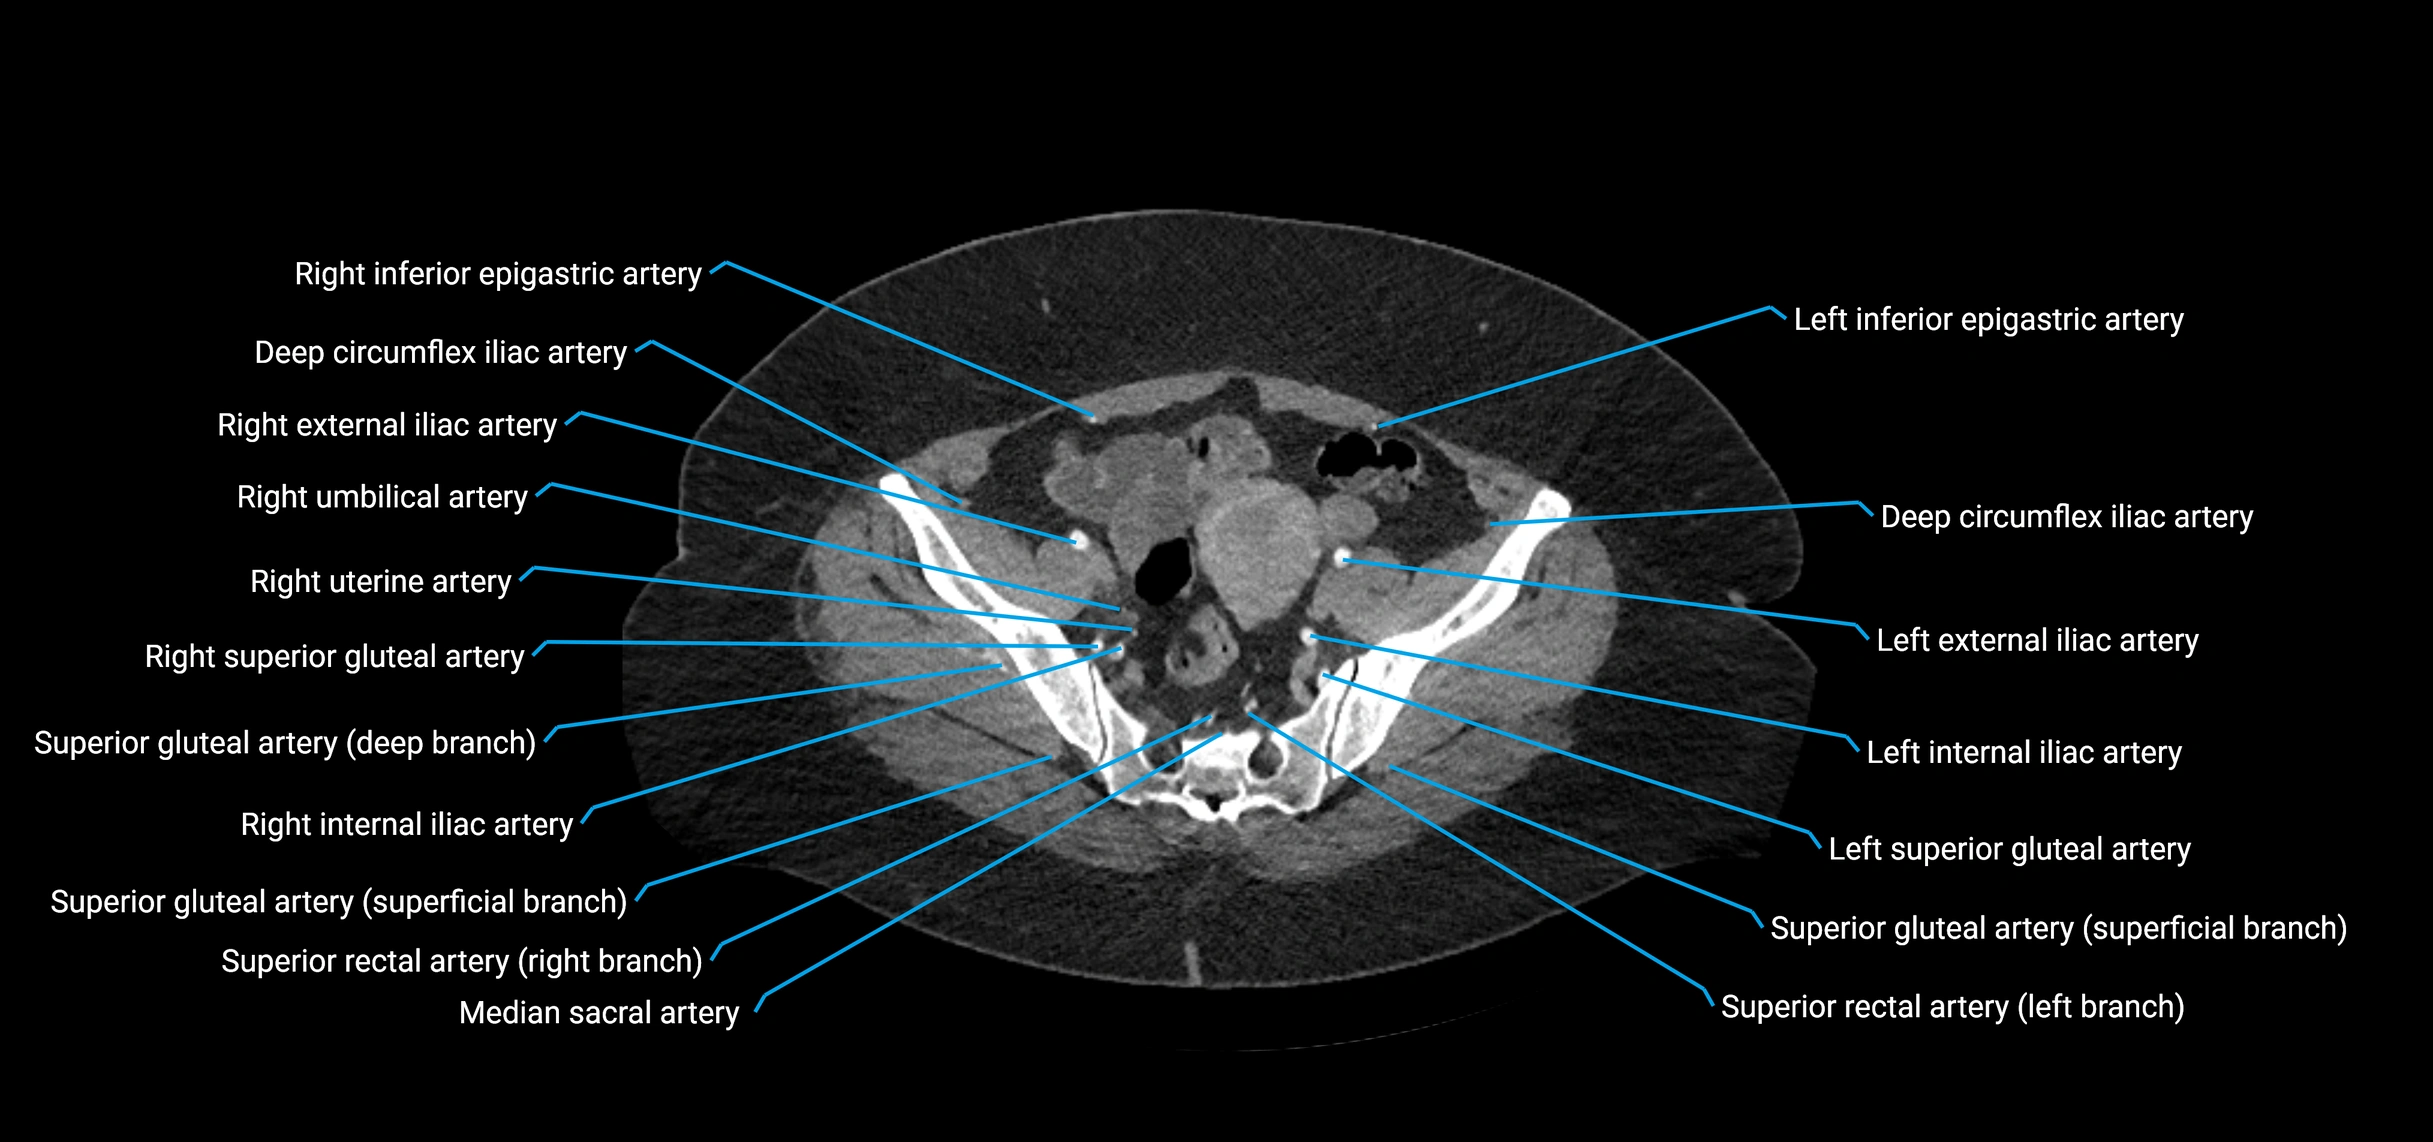

Contrast-enhanced CT (CTA):

• Gold standard for abdominal aortic imaging

• Provides excellent detail of lumen, wall, aneurysm, thrombus, and branch vessels

• Multiplanar and 3D reconstructions help in aneurysm measurement, stent graft planning, and dissection evaluation

• Detects acute rupture, traumatic injury, or occlusion with high sensitivity